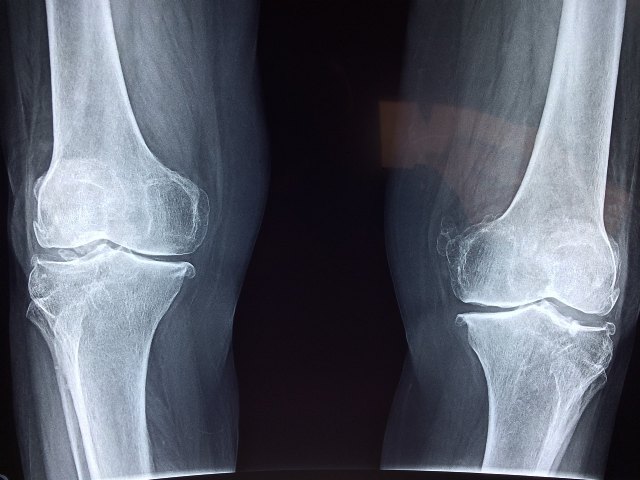

La Hemofilia es una enfermedad rara que se estima que padecen alrededor de 400.000 personas1 en el mundo y que está causada por la falta del factor de coagulación VIII (FVIII) o IX (FIX). Esta deficiencia de factor de coagulación está relacionada con un excesivo riesgo de sufrir hemorragias, bien sea en respuesta a un traumatismo, aunque sea menor, o bien de forma espontánea, sobre todo en articulaciones o músculos.

"La calidad de vida de las personas afectas de hemofilia está relacionada, entre otros aspectos, con la artropatía hemofílica y el dolor articular. Gracias al tratamiento farmacológico hemostático los pacientes pueden hacer ejercicio y deporte, así como llevar un estilo de vida activo, lo que redundará en una buena salud articular, previniendo la aparición o empeoramiento del daño articular", afirma Sofía Pérez.